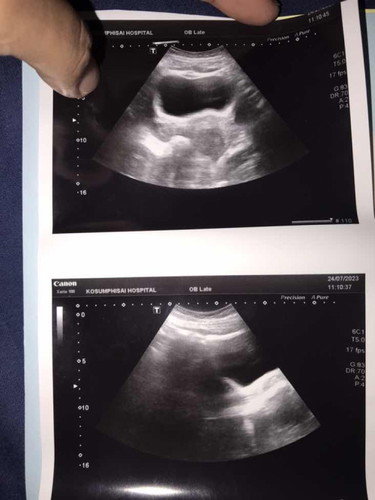

เป็น ปจดล่าสุดวันที่2มิ.ย66 ตรวจเจอว่าท้องวันที่16ก.คค่ะ คุณหมอว่าได้7สัปดาห์แล้วค่ะหมออัลตราซาวด์แล้วไม่เห็นน้องเลยค่ะกังวลมากๆ

บ้านนี้ได้6สัปดาห์หมอนัดให้ไปซาวส์มาเห็นแต่ถุงตั้งครรภ์ยังไม่เห็นน้องเลยหมอนัดไปซาวส์รอบใหม่อีก1เดือนรอลุ้นเหมือนกันค่ะ

วันนี้หมอนัด เจอแต่ถุงยังไม่เจอน้องเราก็กังวลเหมือนกัน

เห็นแค่ถุงตั้งครรภ์จริงๆค่ะ

เท่ากันเลยคะยังไม่เจอน้องเหมือนกันเจอแต่ถุงการตั้งครรภ์ยาว2เซ็น